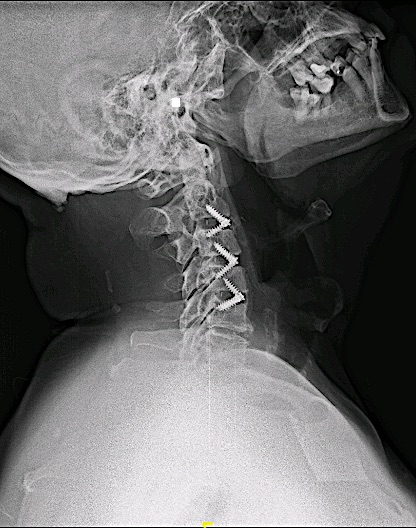

Control de 6 meses

El control postoperatorio RM cervical 6 meses demuestra adecuada descompresión de canal y adecuada aceptación de material de osteosíntesis.